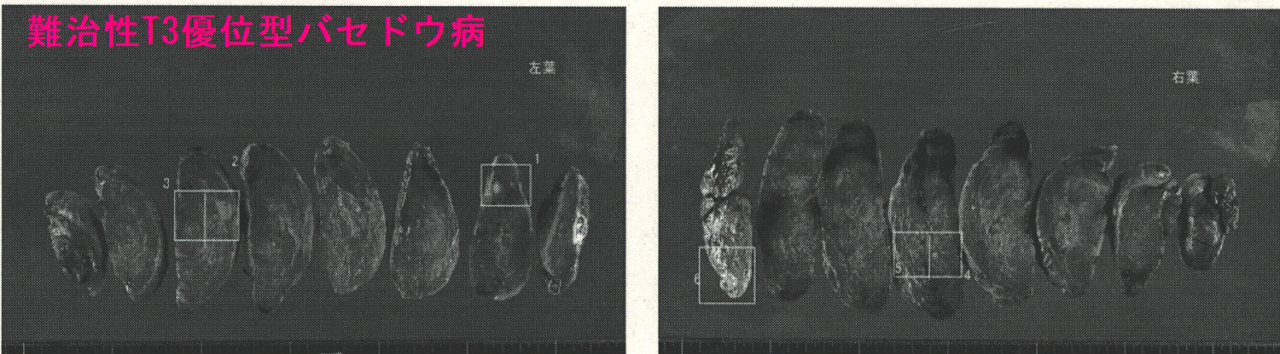

下は、手術標本。一部、エコーでも写らなかった乳頭状増殖(□)を認めたが、悪性所見なし。